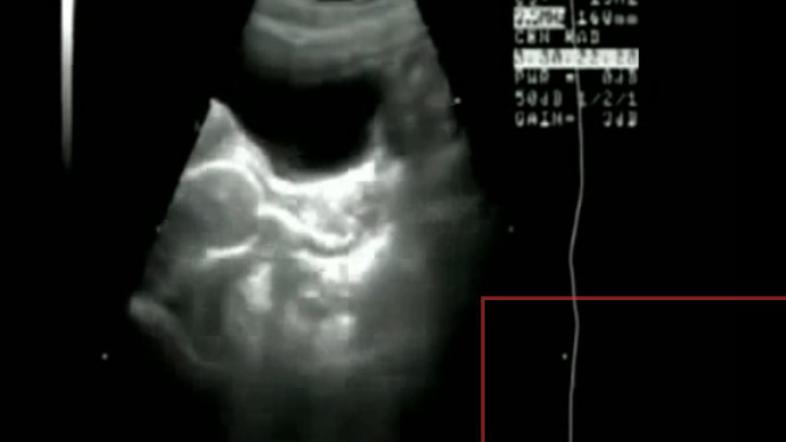

Tako bi seks videl Superman

Raziskovalci so našli par, ki se je strastem v imenu znanosti predajal v aparaturi za magnetno resonanco.

Seks je zdrav. Tisti, ki se lahko pohvalijo z redno posteljo telovadbo, imajo močnejši imunski sistem, stabilen krvni tlak in manj možnosti za nastanek bolezni srca in ožilja. Če vas zanima, kako bi ga s svojim rentgenskim vidom videl Superman, si oglejte video.